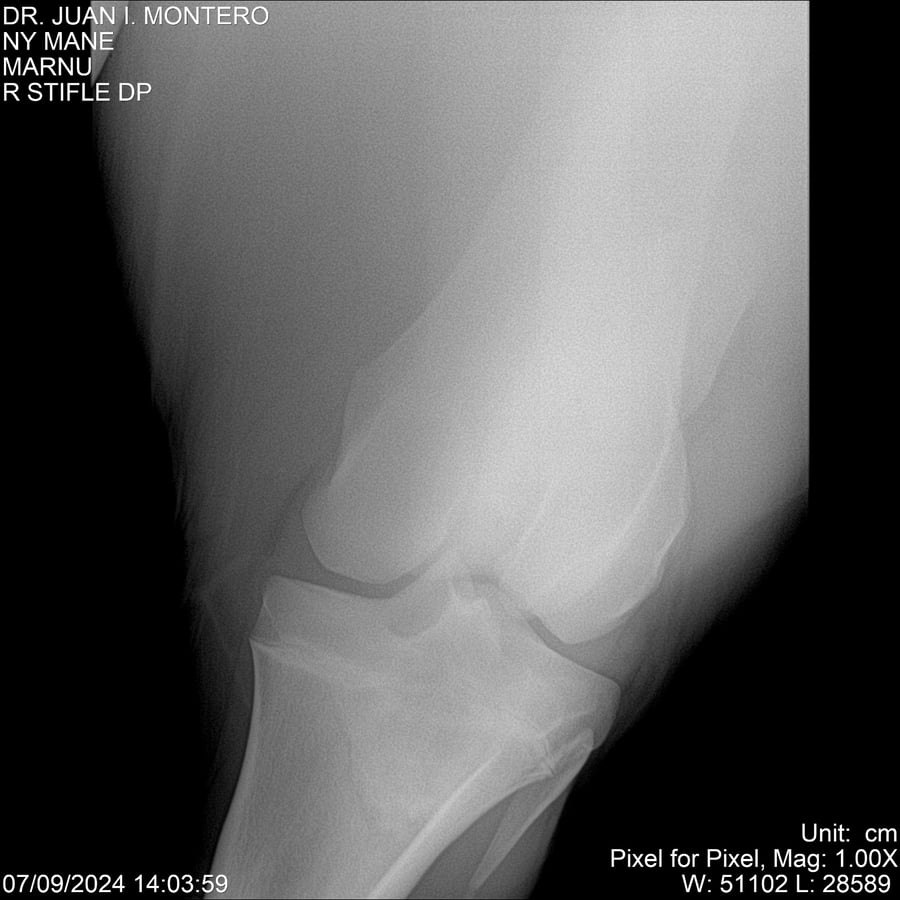

LOTE 20, NY MANE Lote Anterior Volver al remate Lote Siguiente Ficha Contacto Montevideo - Ficha del Lote Identificador: #282520 Categoría: Yeguarizos 76 Visualizaciones ClicData Contacto Empresa: Abelenda N. R., Walter Hugo Nombre*: Teléfono* : E-mail* : Mensaje Enviar Registrese gratis Este contenido Exclusivo está disponible sólo para usuarios registrados Ingresar